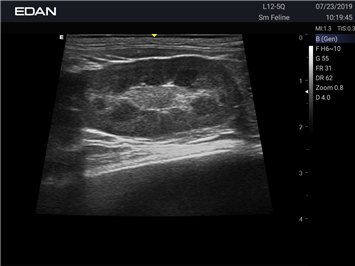

EDAN Acclarix AX2 VET

Ветеринарный ультразвук одним нажатием. Система Acclarix AX2 VET разработана с целью обеспечить бескомпромиссную производительность по доступной цене. Наличие уникальных двойных аккумуляторов в легком корпусе массой 4,5 кг из магниевого сплава позволяет системе Acclarix AX2 VET удовлетворять все потребности ветеринарных исследований, сохранив низкую стоимость.

EDAN Acclarix AX2 VET представляет собой специализированную ветеринарную ультразвуковую систему, сочетающую высокую производительность с доступной ценой. Благодаря продуманной конструкции и передовым технологиям, система обеспечивает качественную диагностику животных различных видов.

B-режим, Двухмерное сканирование:

Да